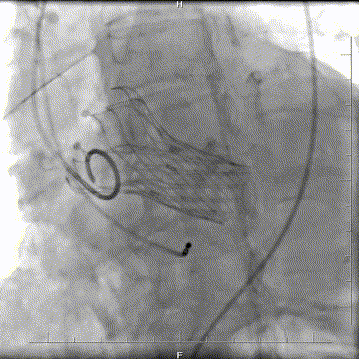

复查造影:瓣膜支架系统膨胀,微量瓣周漏,冠脉显影正常,测量压力阶差5mmHg;术后超声再次评估瓣膜形态,位置可,未见明显反流,手术圆满完成。

术后造影